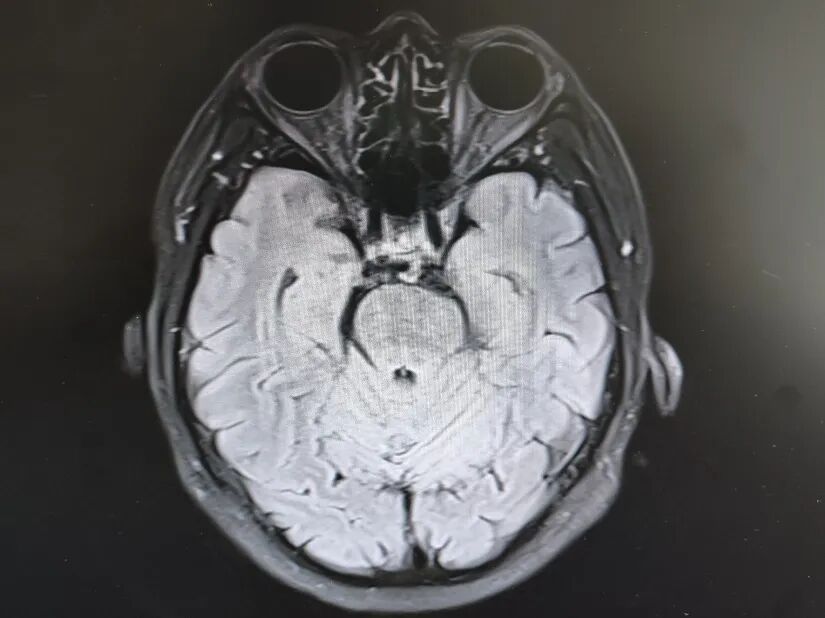

引言 生活中,很多人会突然出现“看东西重影”的情况,往往以为是眼睛疲劳或近视加深,并没有太当回事。然而,这背后可能隐藏着甲亢、脑梗、重症肌无力甚至肿瘤等十余种疾病的信号,是一个需要警惕的“隐形杀手”。 面对这类病因错综复杂的“复视”患者,市二院神经内二科赵智江主任带领团队,凭借丰富的临床经验和深厚的神经疾病诊疗功底,抽丝剥茧,多次成功揪出导致视物成双的“真凶”,为患者赢得了宝贵的治疗时机。 Part.01 复视背后,病因五花八门 神经内二科团队诊治了多位以“视物成双”为主诉的患者,其最终病因各异,充分体现了神经科疾病“同症异源”的复杂性。 以为是眼病,其实是甲亢 患者因复视就诊,经查双眼突出,影像检查发现控制眼球的肌肉异常肥厚。结合甲状腺功能检查,最终确诊为“甲亢性眼肌病”,其原因在甲状腺功能亢进的眼部表现。后经针对性纠正甲状腺功能,患者复视症状显著改善,眼外肌肥厚得到有效控制。 眼眶核磁 甲功结果 眼球状态 复视眼痛,原是痛性眼肌麻痹 患者右眼不仅看东西重影,还出现上睑下垂、眼痛等症状。团队排除其他可能后,诊断为痛性眼肌麻痹(Toloas-Hunt综合征),这是一种自身免疫性炎症。经治疗,患者眼睑下垂症状减轻,眼痛及复视基本消失,眼球运动范围显著恢复。 梅毒隐匿,损伤颅神经 患者因眼皮抬不起、眼球转动不灵并视物重影入院。常规血清检查发现梅毒抗体阳性,排除其它原因导致的复视,最终明确为“神经梅毒”侵蚀颅神经所致。确诊后立即给予驱梅治疗,效果明显,眼皮能抬起来了,重影消失了,眼球转动也灵活了。 糖尿病悄悄损伤神经 两位糖尿病患者,均以突发复视就诊。团队精准判断,发现分别是高血糖损伤了“动眼神经”和“外展神经”,属于糖尿病性单神经病变,表现为不同类型的复影(上下重影或水平重影)。明确诊断后,经严格控糖,辅以营养神经药物等综合对症治疗,患者病情好转,顺利出院。 脑梗“瞄准”不同区域 三位患者均因复视就诊,但伴随症状各异,有的行走不稳,有的走路右偏。赵智江主任团队通过精细的神经系统查体,精准定位于中脑的动眼神经核、桥脑的内侧纵束等。不同脑区梗死,复视的表现也完全不同。后通过溶栓药物、抗血小板药物、改善循环治疗等针对性治疗,辅以康复治疗,患者身体逐渐好转,出院时已无视物成双症状。 三位患者的核磁 典型信号——晨轻暮重 患者出现复视,伴言语不利、吞咽困难、饮水呛咳等症状。其中复视有个鲜明特点——早晨轻、傍晚重,疲劳后加重。经专项检查,确诊为“重症肌无力”(眼肌型)。这是一种神经肌肉接头疾病,免疫调节治疗可有效控制。经过一段时间的治疗,患者复视症状明显缓解,言语不清、吞咽困难症状得到显著改善。治疗前患者只能进食流食,治疗后可自主进食固体食物。 肿瘤病史者,需警惕转移 淋巴瘤患者在化疗期间出现复视和面瘫。团队通过脑脊液等深入检查,排除感染等因素,最终诊断为脑膜癌病。 嗜睡头晕,病因在营养 患者急性起病,表现为复视、头晕、嗜睡、走路不稳。团队结合其既往史和典型眼球活动障碍,迅速锁定病因——因维生素B1严重缺乏导致的“韦尼克脑病(Wernicke)”。补充维生素B1一周以后,患者复视症状改善、走路平稳、神志清楚,可独立行走。 Part.02 精准诊疗,揪出“元凶”是关键 赵智江主任指出:“复视只是一个临床症状,其背后可能是内分泌、炎症、代谢、脑血管、自身免疫、肿瘤等多种病因在神经系统上的投射,涉及学科广泛。” 市二院神经内二科团队通过详细追溯病史、进行一丝不苟的神经系统专科查体(尤其是眼球运动检查),初步判断病变可能位于动眼、滑车、外展神经的神经核团,神经及其所支配的肌肉、神经-肌肉接头等部位,然后精准选择并解读影像学、免疫学、生化及脑脊液等检查结果,最终整合信息,明确诊断,为患者制定出针对性的治疗方案。 市二院神经内二科在赵智江主任的带领下,始终致力于复杂疑难神经系统疾病的诊疗攻坚。科室凭借严谨的临床路径、对神经解剖与病理生理机制的深刻把握,以及精湛的诊疗技术,为众多罕见病与危重患者精准定位病因、制定个体化治疗方案,有效提升了救治成功率与患者长期生活质量。 提醒市民:如果突然出现视物重影,尤其是伴有眼皮下垂、眼球转动不灵、疼痛、头晕、行走不稳或其他神经系统症状时,切勿掉以轻心,应及时重视,这些症状有时可能与神经系统疾病相关。为了明确原因,获得更全面的评估,您可以考虑到神经内二科就诊,由专业医生进一步检查与诊断,以便尽早获得适合的照顾与治疗。 Part.03 人民医院 人民名医 赵智江 主任医师 副教授 ·葫芦岛市第二人民医院神经内二科主任 ·中国卒中学会高级会员 ·中国老年保健医学研究会老年脑血管病分会委员 ·北京神经内科学会脑小血管病学会委员 ·安徽医药杂志审稿专家 ·辽西神经疾病专科联盟理事 ·辽西认知功能障碍联盟理事 ·辽西神经免疫学会委员 ·葫芦岛市医学会神经病学分会委员 专业特色:以脑血管病为核心研究方向,擅长各类神经系统疾病的诊疗,尤其在脑血管病、帕金森综合征、头晕、头痛、癫痫、重症肌无力、多发性硬化等神经免疫性疾病以及其它神经系统疑难、危重疾病的诊疗方面积累了丰富的临床经验。 出诊时间:每周一、周四全天 咨询热线:0429-8010317